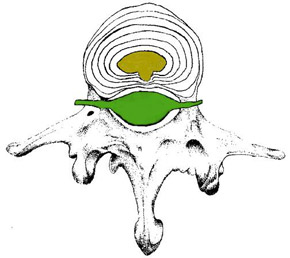

A differenza della protrusione in cui assistiamo ad una dislocazione del materiale nucleare all'interno del disco intervertebrale il cui meccanismo idrostatico resta integro (danno discale riducibile [2] trattato efficacemente con la metodica McKenzie),

Rappresentazione di una protrusione discale centrale